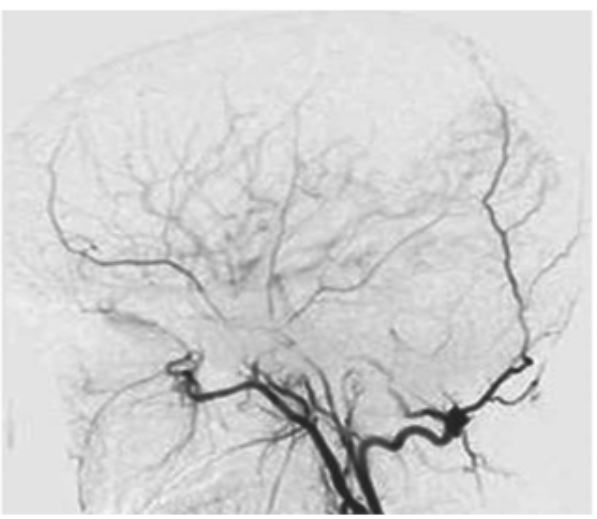

- 우리 뇌의 바닥 쪽에 있는 뇌혈관 중 내경동맥의 끝부분과 이와 연결된 대뇌동맥고리(월리스 동맥륜)가 안쪽부터 두꺼워지면서 혈관이 막히면서 이런 혈관을 대신하기 위해 가느다란 혈관들이 생겨나는 희귀병을 얘기합니다.

- 1960년대 일본에서 뇌혈관 조영술을 연구하다 발견해 혈관 모양이 연기가 모락모락 올라가는 것처럼 보인다고 하여 모야모야병이 이라고 이름을 붙였습니다.

- 증상이 반복되면 수술적 치료를 고려하며, 뇌에 공급하는 혈류를 증가시키기 위해 막힌 혈관을 정상 혈관과 이어주는 혈관 문합술을 하게 됩니다.